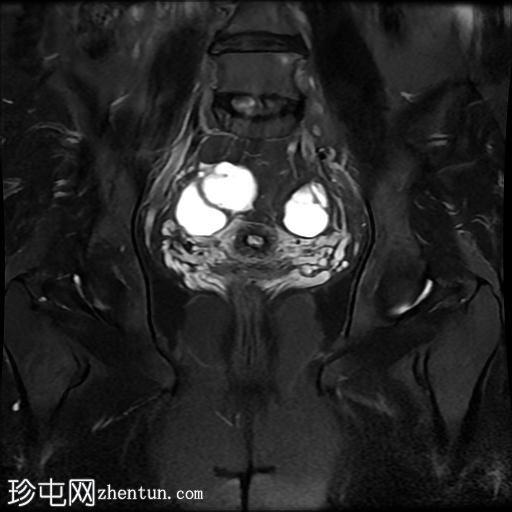

冠状位T2加权像

脂肪抑制像

右侧输卵管呈管状囊性扩张,直径达30 mm,提示输卵管积水,呈均匀液体信号,无实性成分。

左侧输卵管亦有轻度扩张,直径26 mm,符合输卵管积水表现。

右侧卵巢可见一单纯性卵巢囊肿,大小约35 x 40 mm,呈正常液体等效信号。

宫内节育器位置正常。

MRI 检查结果显示双侧输卵管积水和右侧卵巢单纯性囊肿。总体而言,所有附件和盆腔检查结果均显示良性 MRI 特征(O-RADS 2 类),无恶性肿瘤迹象。